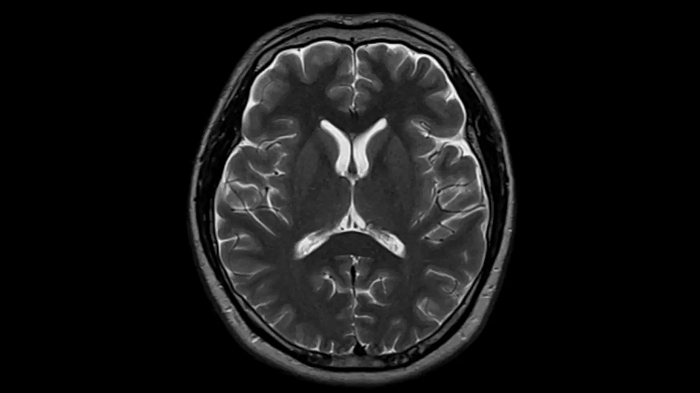

Head

T2 TSE with Deep Resolve

To produce high-resolution images, Deep Resolve, the Al-powered image reconstruction technology gets benefits from intelligent denoising and neural networks.

Deep Resolve Gain & Sharp

0.4 x 0.4 x 5.0 mm2

TA 2:50 min